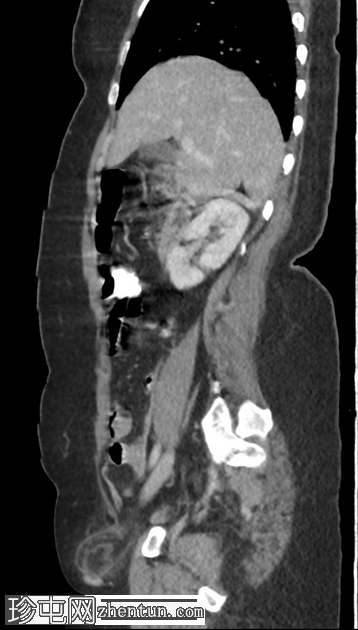

CT扫描

轴向C+门静脉期

右腹股沟疝,内含脂肪。疝颈位于下腹壁动脉起点下方。疝囊压迫股总静脉。脂肪含量不均质,脂肪条带状排列,并有微量液体,提示为嵌顿性股疝。

可见少量腹股沟淋巴结轻度肿大。